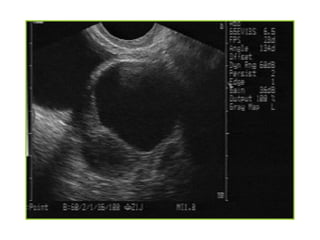

Abnormal IUP

 A GS larger than 10-13 mm diameter(TV) or 20mm (TA)

without a yolk sac

 A GS larger than 18 mm (TV) or 25mm (TA) without a

fetal pole

 A definite fetal pole without cardiac activity after 7 wks

GA

Empty gestational sac

Fetal demise